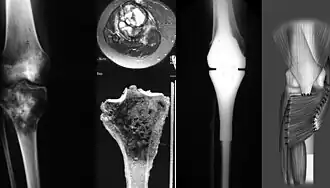

Un ostéosarcome (sarcome ostéogène, du grec ὀστέον ostéon os[1] et σάρκωµα sarkôma excroissance de chair[2]) est la plus courante des tumeurs malignes osseuses primaires, chez les adolescents et jeunes adultes (10-25 ans). Il a une prédilection pour la région des métaphyses des os longs tubulaires et 50 % des cas se produisent autour du genou.

La tumeur est solide, dure, irrégulière, (décrite en « sapin » ou en « rayon de soleil » sur les examens aux rayons X) en raison des spicules tumorales d'os calcifiés rayonnant en angle droit. Ces angles droits forment ce que l'on appelle un triangle de Codman. Les tissus environnants sont infiltrés.

Le diagnostic de cette pathologie est suggéré à l’aide de techniques d’imageries comme la radiographie, l’IRM, la scintigraphie osseuse, la tomodensitométrie, puis confirmé par biopsie[11],[12].